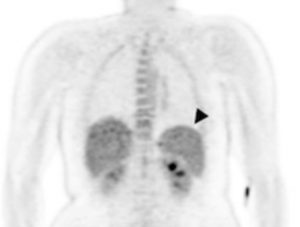

En la imagen por PET se observa el aumento de la captación de la glucosa en el brazo después de la infección por malaria.